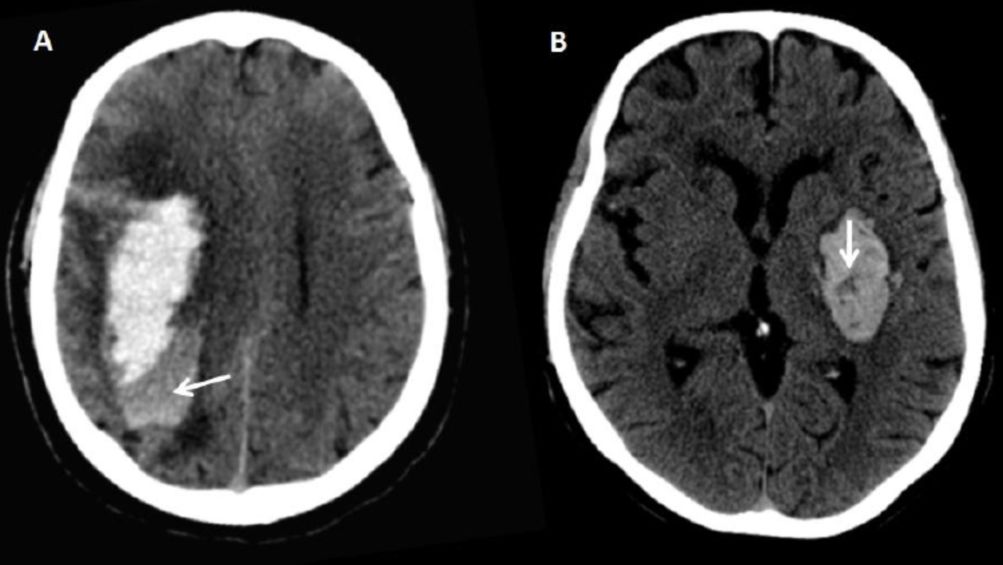

研究结果发现,混合征(blend sign)(OR=3.09;95% CI,1.49-6.40;P=0.002)、黑洞征(intrahematoma Hypodensity)(OR=4.54;95% CI,2.44-8.43;P<0.0001)和发病到NCCT的时间<2.5小时(OR=3.73;95% CI,1.86-7.51;P=0.0002)是预测脑出血后HE的独立危险因素。基于以上指标,作者提出BAT评分,即5分计分法(图1、表1)。

图 1. A.CT平扫示脑出血的混合征表现(箭头所示部位);混合征指血肿中出现既相邻又有清楚分界的高低密度区,密度相差至少18HU,低密度区不被高密度区包裹。B.CT平扫示脑出血的黑洞征表现(箭头所示部位);黑洞症指在血肿高密度区内边界清楚的低密度灶,其 CT值至少比周围的血肿区小28HU。